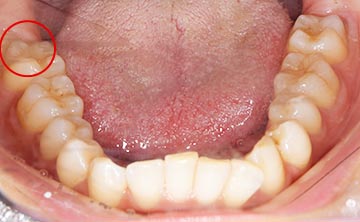

麻布十番歯科で親知らずが横向きに生えて歯ぐきが腫れている症例の口腔内写真のイメージ

親知らずを抜くのに痛みを伴いやすいものが写真とレントゲンにあるような真横にはえているもの、もしくは斜め下にはえている下顎の親知らずです。また、根が曲がっていたり、数が多いほど抜くのが難しい経口にあります。

この場合、歯ぐきを切ったり、歯を囲っている周りの骨を削って抜いていかなければなりません。